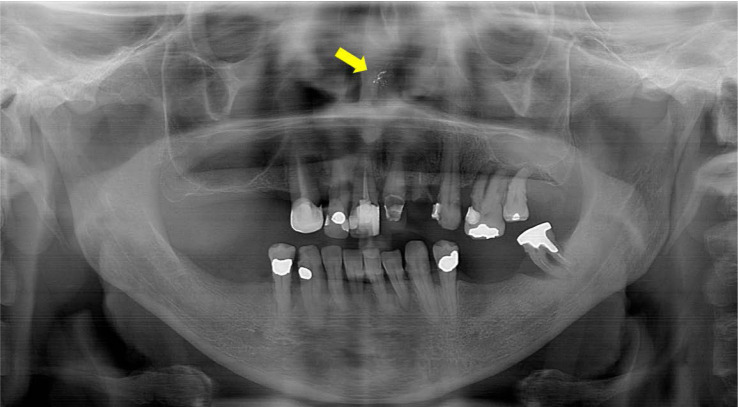

Nasal myiasis is an infestation by dipterous larvae within the nasal cavity, where they feed on both living tissue and fluid. This condition predominantly occurs in rural areas of tropical countries, where inadequate sanitation and a hot, humid climate create an ideal environment for larvae development. A 57-year-old, otherwise healthy male rural worker presented with a toothache in the region of the maxillary incisors. Imaging studies identified a punctiform radiopaque/hyperdense area near the nasal septum in the left nasal fossa. The larva was surgically excised and sent for histopathological analysis. Histologic sections confirmed the clinical diagnosis, and the patient remained asymptomatic after a 2-month follow-up. Nasal myiasis can mimic the symptoms of a toothache in the anterior region of the maxilla. This condition can affect even immunocompetent patients, and complementary imaging studies may be decisive in diagnosing it.